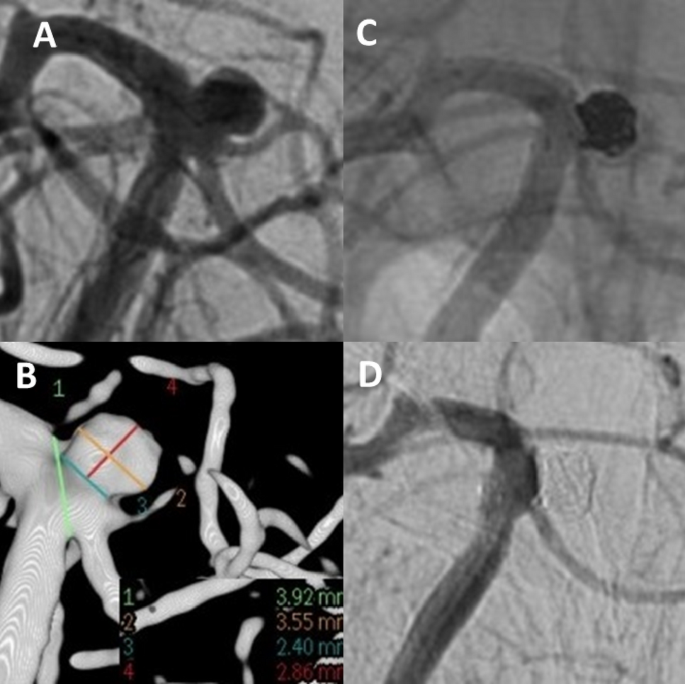

Unruptured aneurysm at the basilar tip (A + B). Stent-assisted coiling was intended. A stent (barrel-3550) with a barrel-shaped central segment was inserted to bridge the aneurysm neck in such a way that both the aneurysm base and the doubled superior cerebellar artery on the left are secured. The aneurysm sac is then probed through the stent mesh with a SL10-MC and closed with a total of 6 platinum micro-spirals. (C) Two-years angiographic control shows complete aneurysm occlusion (D).

In coiling procedures, balloon assistance or stent assistance with Y-, T- or single stenting techniques were used if required at the discretion of the treating neurointerventionalist (Fig. 3). Implanted stent types were: Neuroform EZ and Atlas (Stryker, Alamazoo, MI, USA), Solitaire AB (Covidien, Irvine, CA, USA), eCLIPs (endovascular CLIP System, Evasc, Medical Systems Corp., Vancouver, BC, Canada), LVIS (Micronvention/Terumo, Aliso Viejo, CA, USA), Barrel stent (Barrel Vascular Remodeling Device (VRD) system; Medtronic, Minneapolis, Minnesota, USA), Acclino stent (Acandis, Pforzheim, Germany), LEO Baby (Balt, Duesseldorf, Germany) and Enterprise (Cordis Neurovascular, Miami, FL, USA).